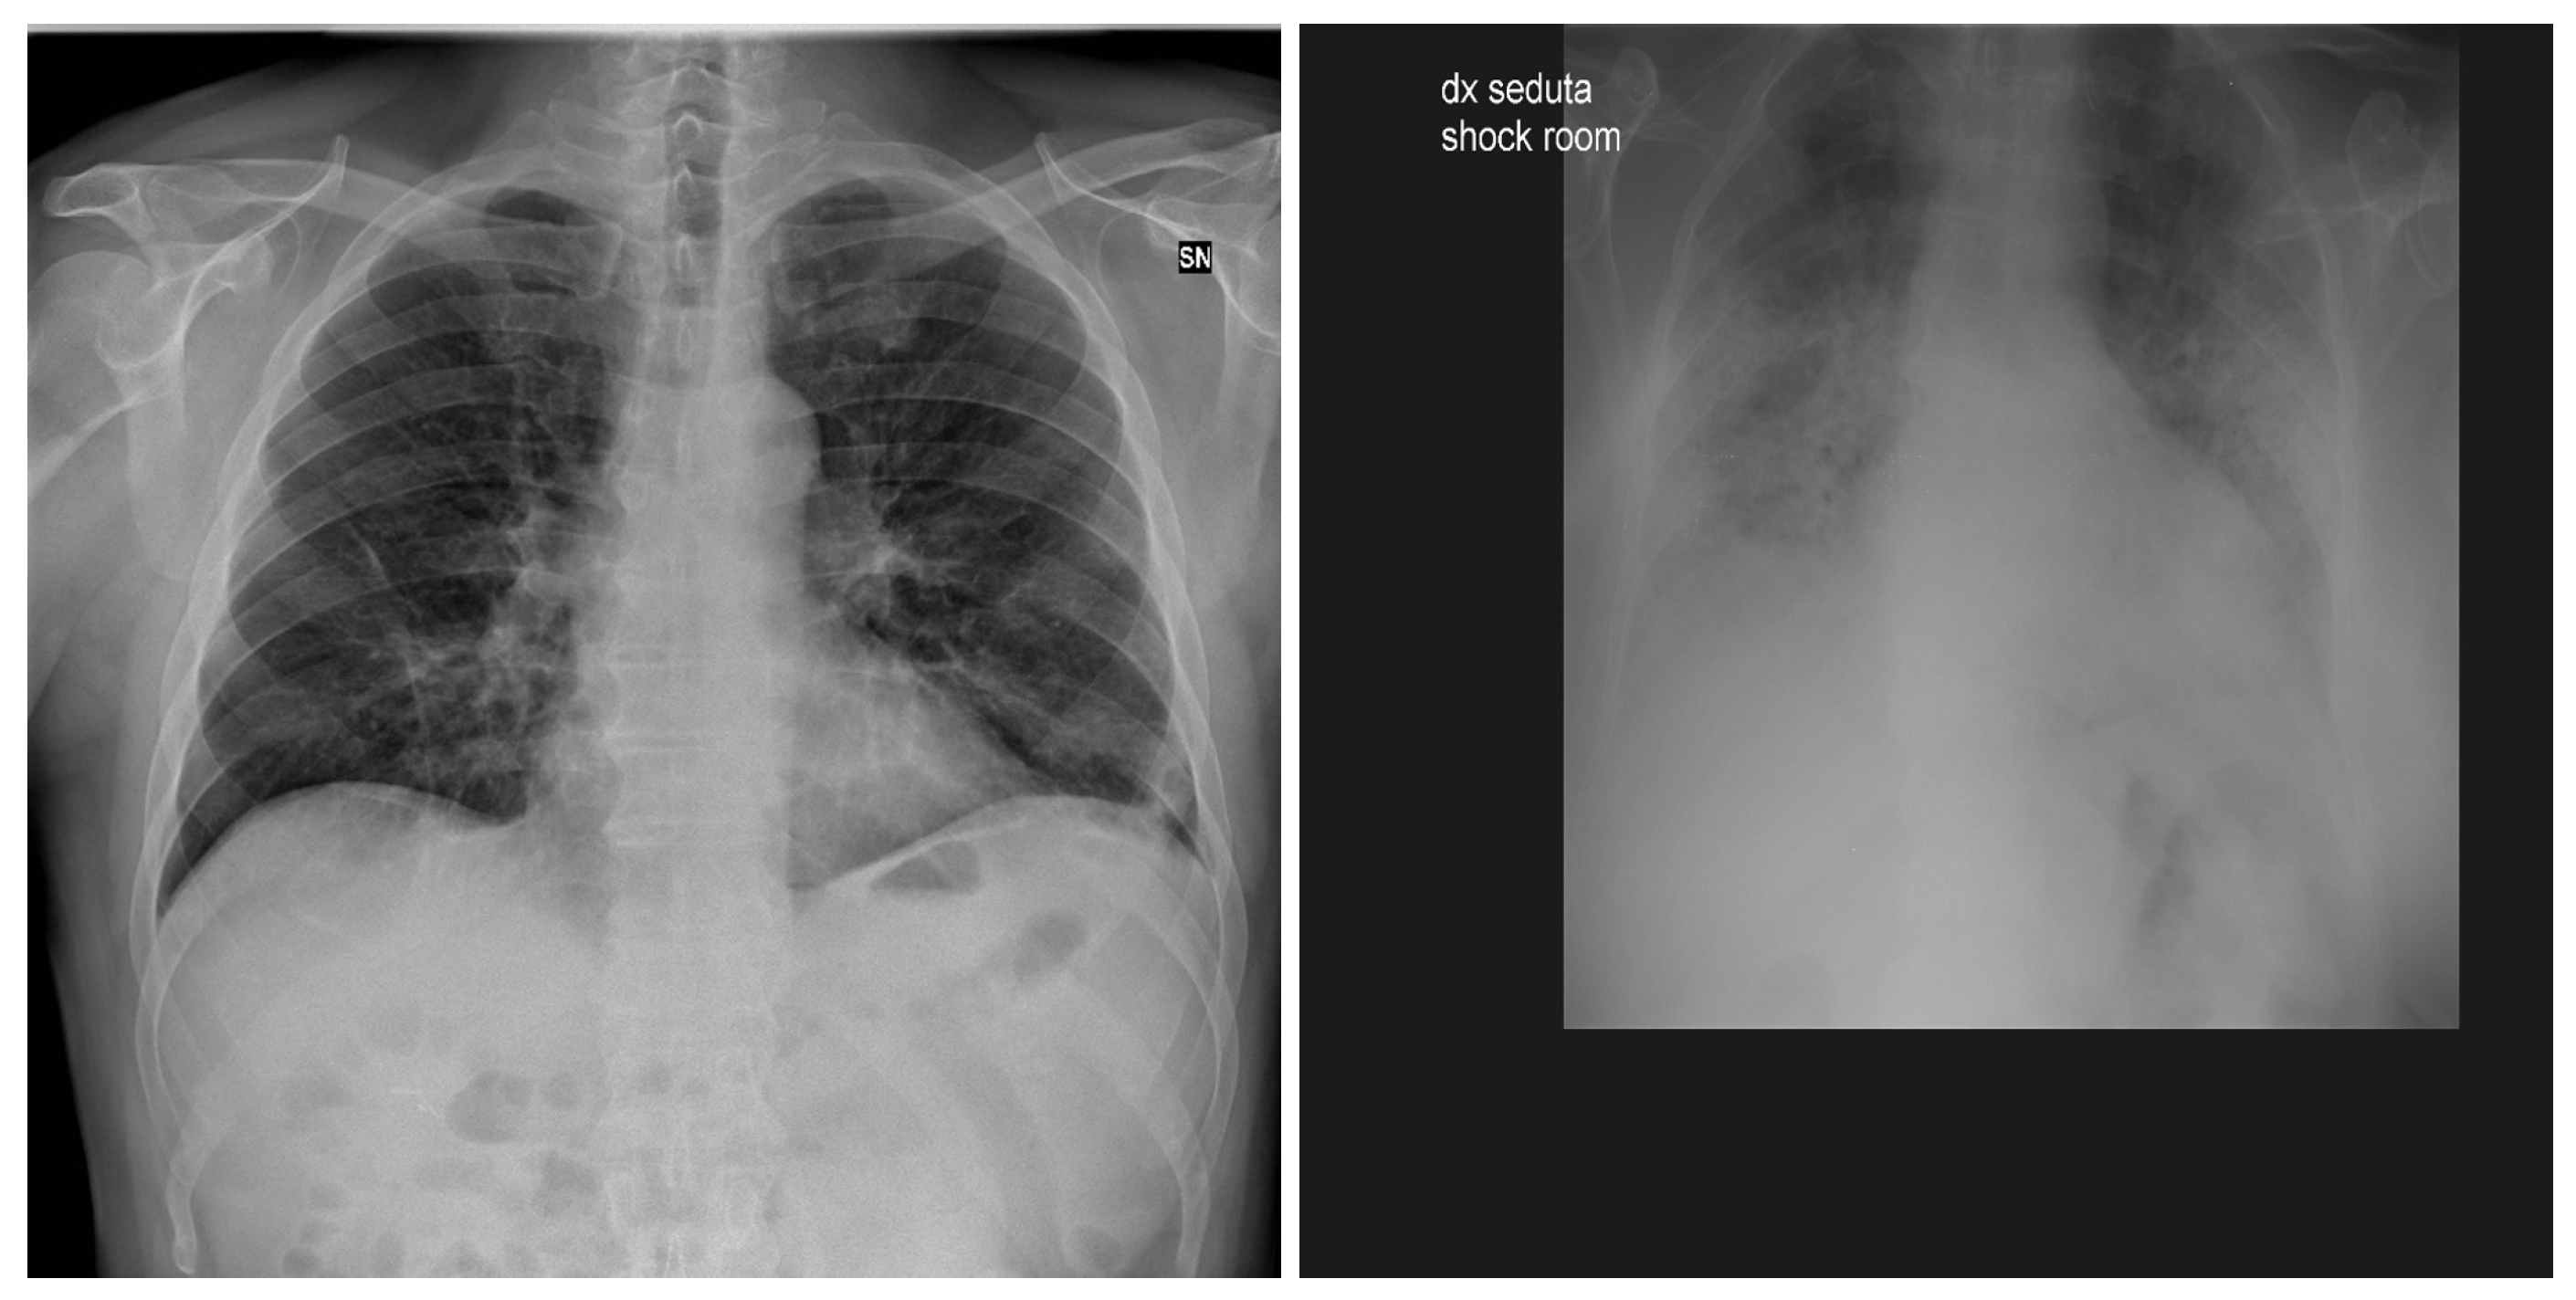

3.5. Chest X-ray Images Pneumonia (CXRIP)

3.6. Montgomery County X-ray

3.7. Shenzhen Hospital X-ray

3.8. National Institute of Health (NIH)